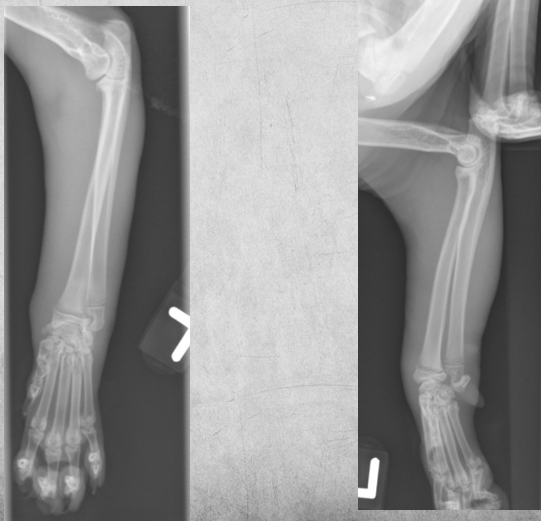

6

Q

4 months old male kitten

Not using left front leg

A

diffuse soft tissue swelling of the left forelimb. The physis of the distal radius has a thin radiolucent line just proximal to it.

7

4 months old male kitten. presenting complaint Not using left front leg.

images from 4 weeks later:

4 weeks later: The soft tissue swelling is decreased.

Both proximal and distal growth plates of the radius are closed.

There is well defined new bone formation, especially at the proximal diaphysis of the radius.